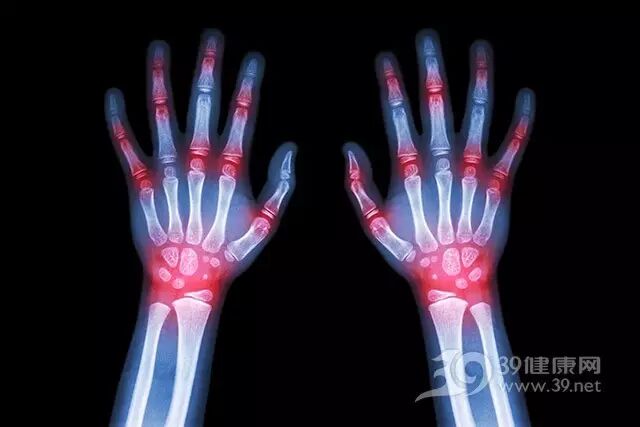

1、抗炎

姜含有强力的抗炎化合物,可以保护身体免受心血管疾病、糖尿病、关节炎、阿尔茨海默病、肺部疾病等的伤害,减轻肌肉和关节的炎症性疼痛。